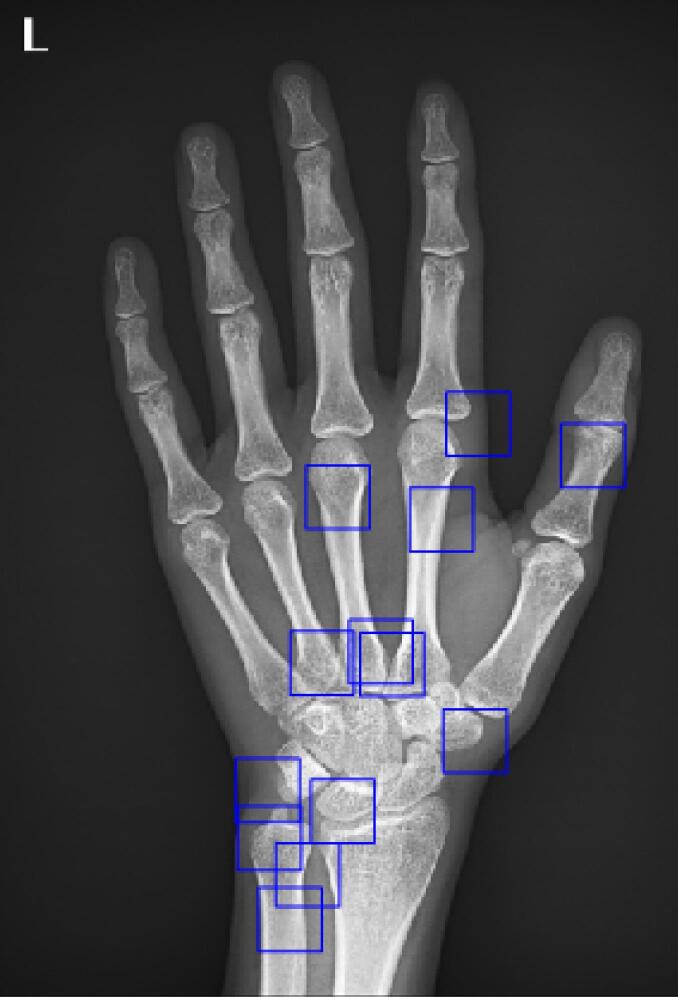

Methods: From left-hand radiographs of children aged 1-18 years who presented to a tertiary research hospital, 555 radiographs (220 boys and 335 girls) were collected. The reference BA was determined via the Greulich and Pyle (GP) method by two radiologists in consensus. The BA was then estimated to use a deep learning model specifically developed for this population. Model performance was evaluated using multiple metrics: Mean square error (MSE), mean absolute error (MAE), intra-class correlation coefficient (ICC), and 95% limits of agreement (LoA). Gender-specific results were analyzed separately.

Abstract Image